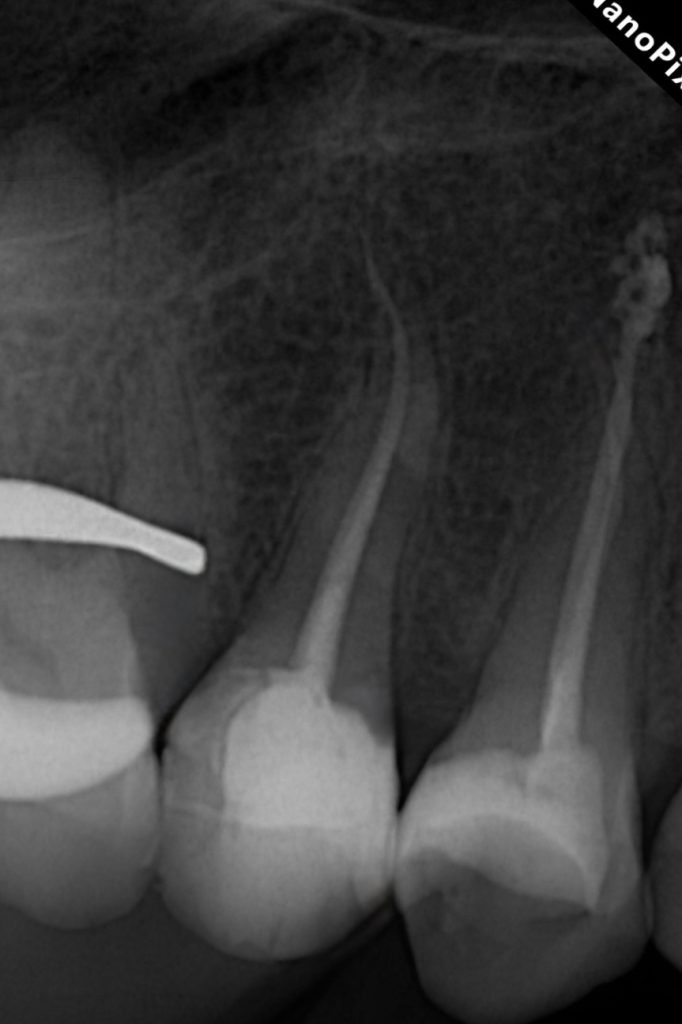

3. Three-Dimensional Obturation

Canals were obturated using a bioceramic sealer and warm vertical compaction technique, confirming dense fill and apical seal. Post-operative radiograph verified optimal obturation and periapical healing potential. (Fig. 7)

- Radiographically: Dense obturation with intact lamina dura and proper apical seal.

Fig. 7: Radiographic confirmation of bioceramic obturation and coronal seal.